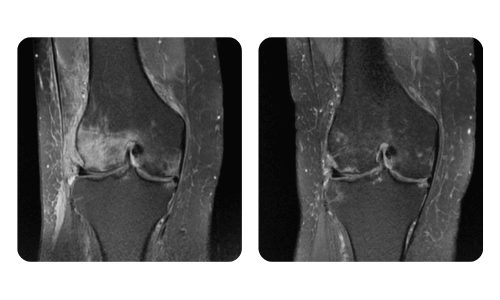

I progressi dei nostri pazienti, misurati prima e dopo la terapia iperbarica, riflettono l'efficacia e l'impatto positivo del trattamento. Scopri i risultati documentati della terapia iperbarica presso la clinica Hyperbarium Oradea, basati su valutazioni cliniche e dati oggettivi che evidenziano miglioramenti significativi in diverse condizioni.